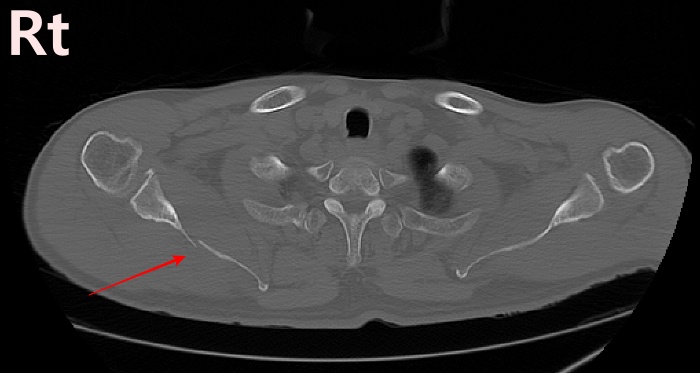

2022.06.07 CT SCAN

- M/50대

- fall down

- X-Ray 검사 상 견갑골 골절의심 됨

- Axial Scan 후 MPR로 Axial, Coronal, Sagittal image Recon 함

- Rib CT 포함하여 검사함.

3.Finding.

4.conclusion

mildly displaced fracture of body of scapula.